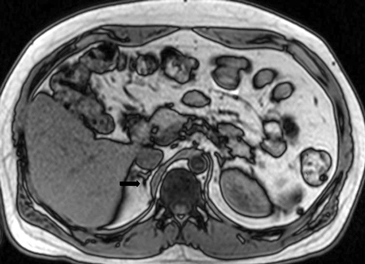

La apariencia en RM es inespecífica, presentando con mayor frecuencia hipointensidad con respecto al parénquima hepático en secuencias T1, hiperintensidad heterogénea en secuencias ponderadas en T2 y ausencia de caída de señal en secuencias fuera de fase, con escaso refuerzo progresivo tras el uso de Gadolinio endovenoso (Figuras 30 a y b).

A

B